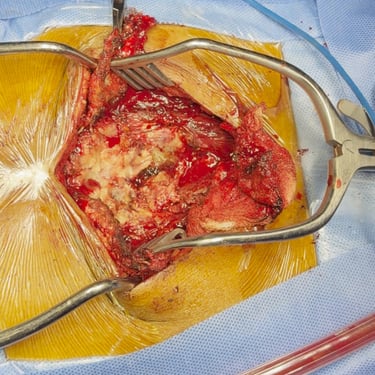

Sarcoma Sacro: Citorreducción Tumoral y Descompresión Nerviosa

El sarcoma sacro es una neoplasia poco frecuente y de manejo complejo que puede generar dolor severo, alteraciones neurológicas y compromiso de la movilidad por afectación de las raíces nerviosas sacras. El tratamiento quirúrgico mediante citorreducción tumoral tiene como objetivo disminuir el volumen del tumor, mientras que la descompresión nerviosa permite aliviar la presión sobre las estructuras neurológicas comprometidas. Este abordaje busca mejorar el control del dolor, preservar la función neurológica y optimizar la calidad de vida del paciente. La planificación cuidadosa y el manejo multidisciplinario son fundamentales para obtener mejores resultados clínicos.